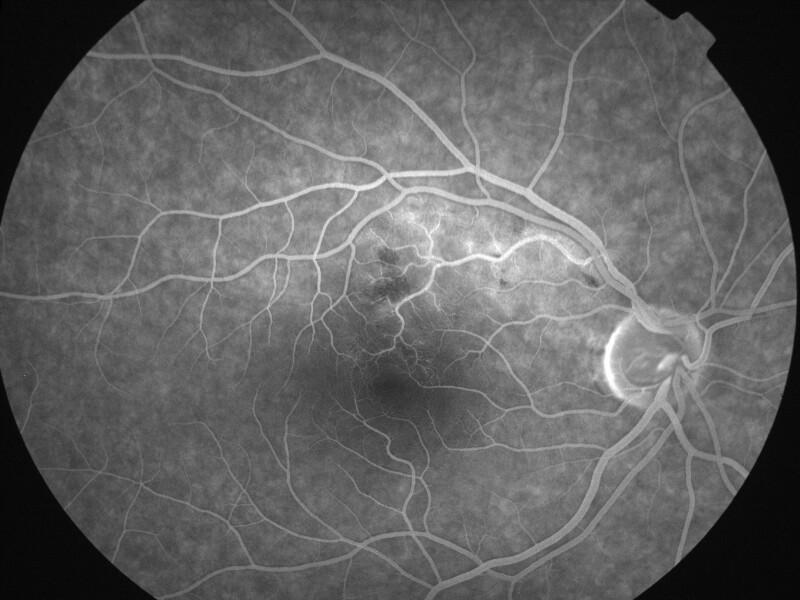

2002080202\02-08-2002